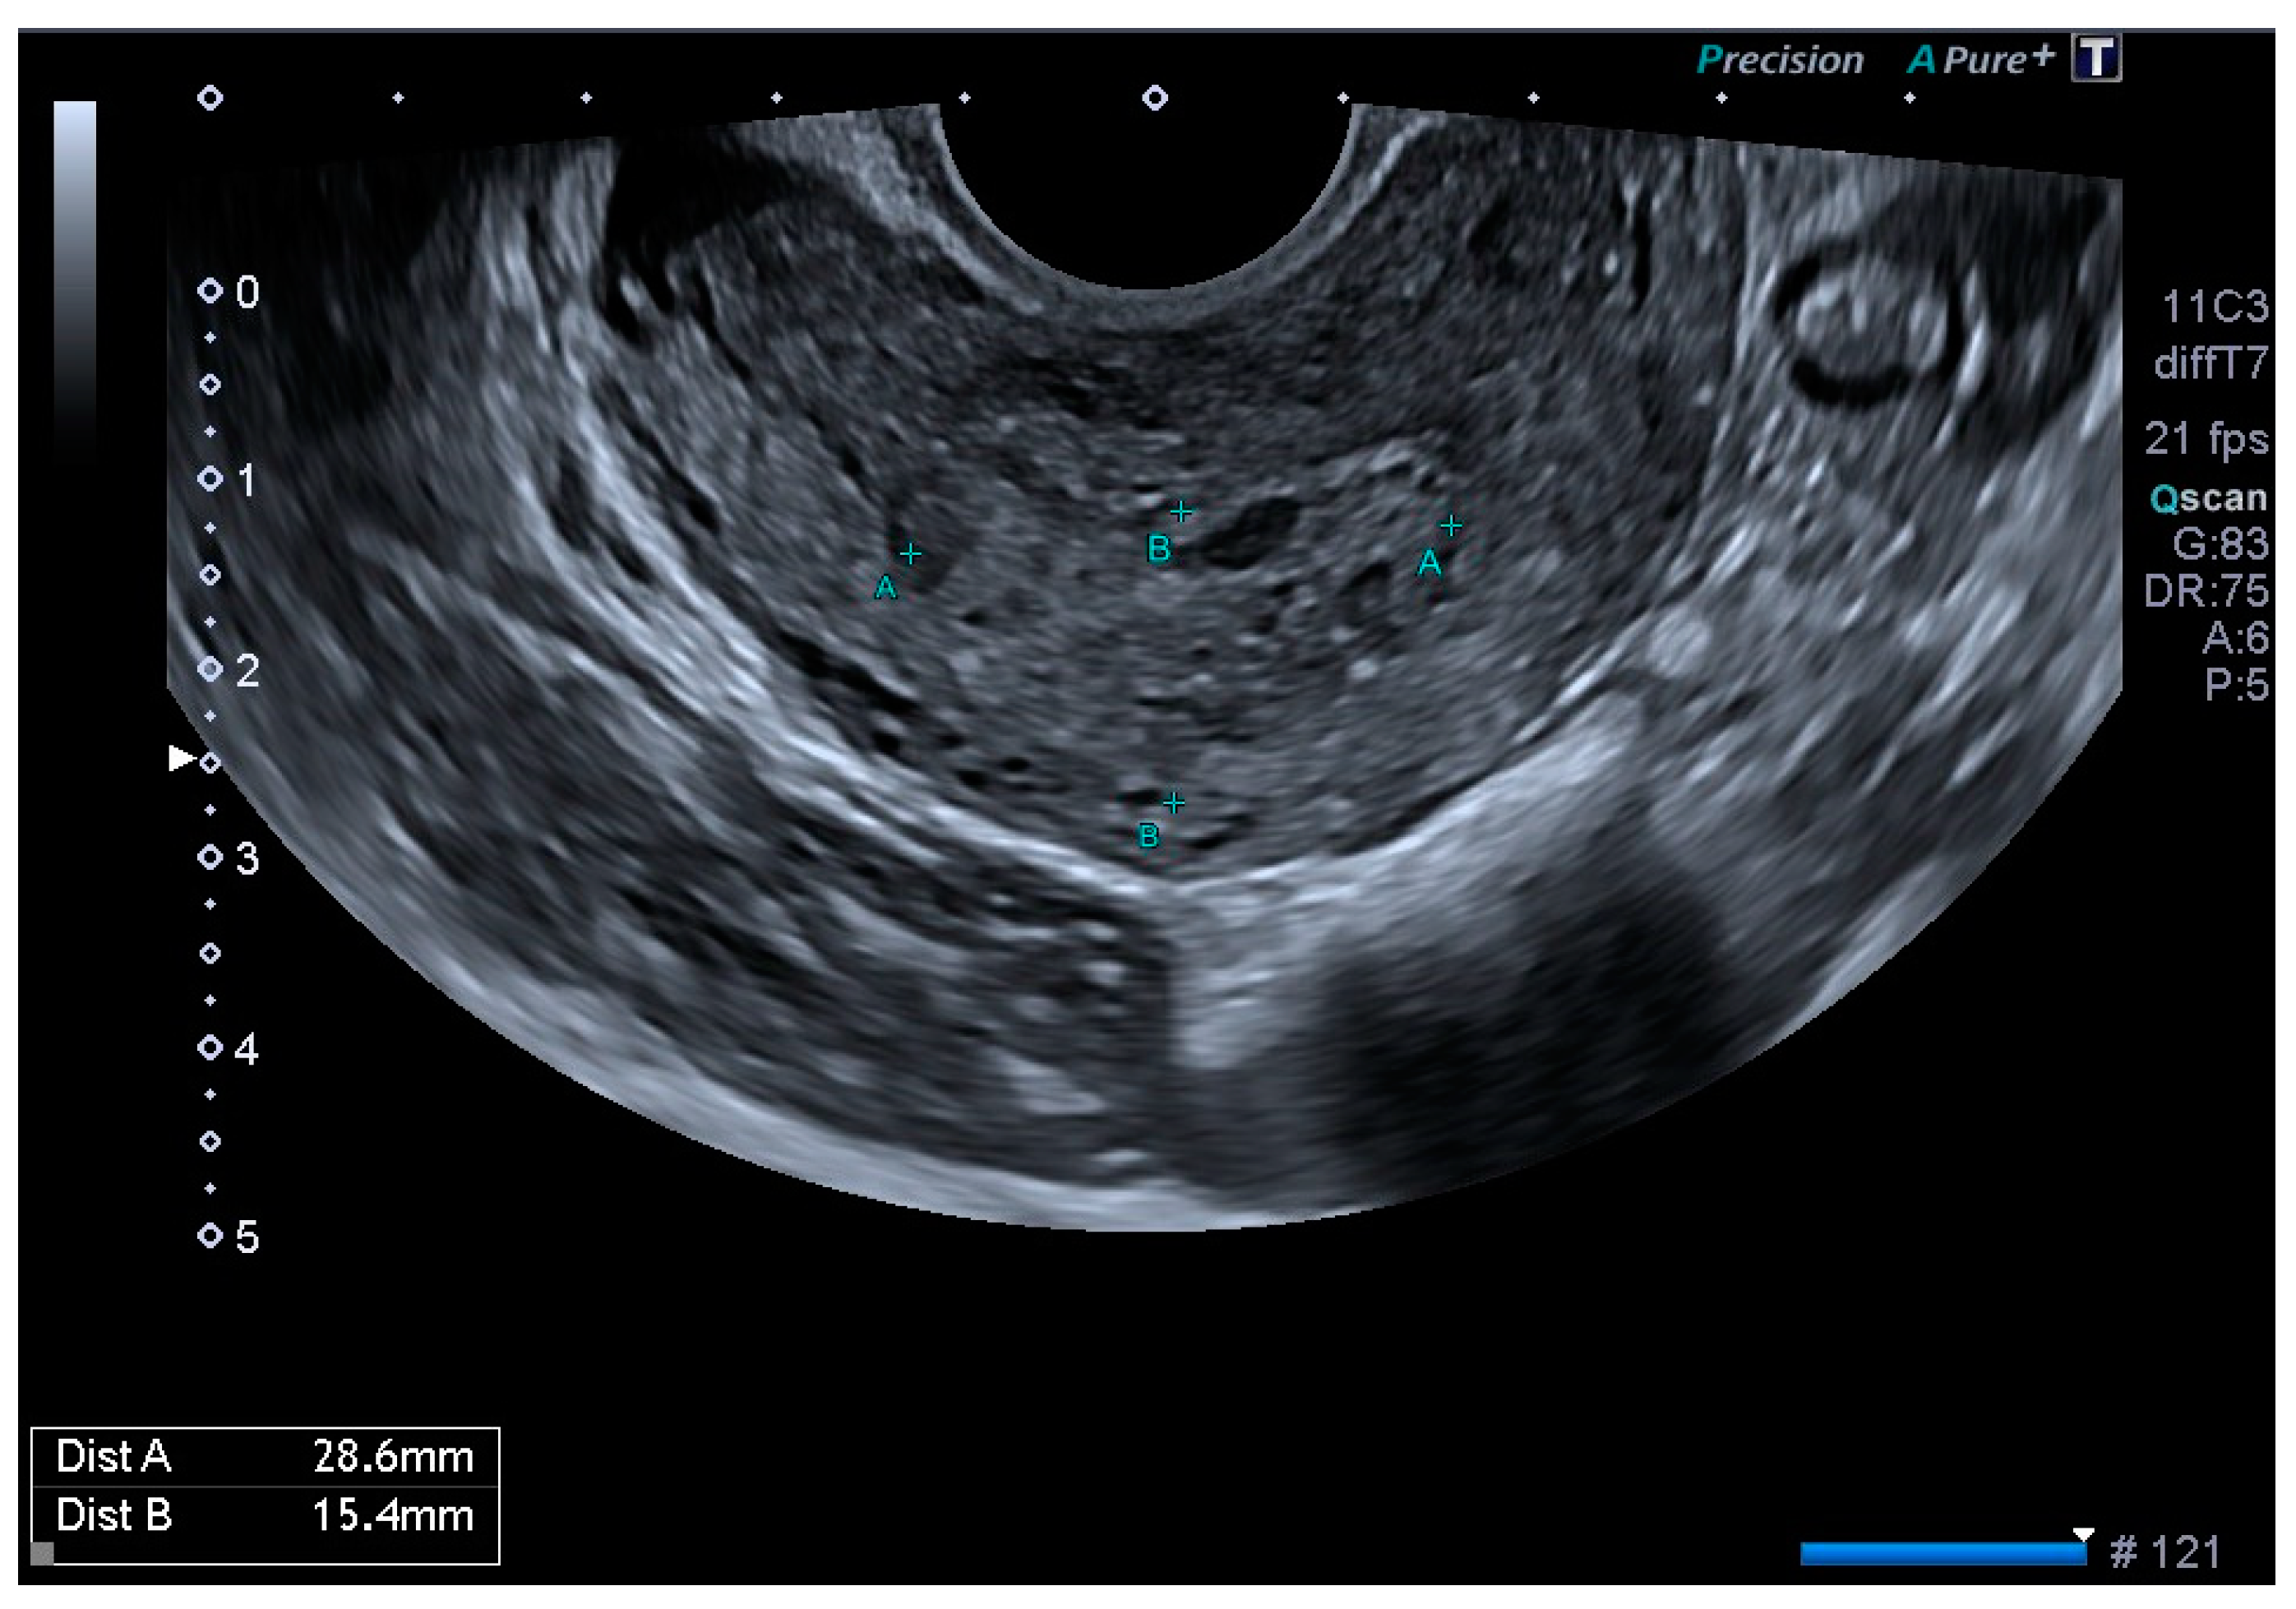

Finally, the vascular surgeons ruled out selective arterial embolisation because the size of the lesion made complete and effective embolisation impossible. Conservative treatment with combined hormonal contraceptives was chosen because the patient’s reproductive desires were not fulfilled. After four months of being asymptomatic and under treatment with combined hormonal contraceptives, the patient presented for follow-up, at which time no AVM was observed on the ultrasound, either in B-mode or colour Doppler (Figure 5 and Figure 6).

Figure 5. Linear endometrium after conservative treatment for 4 months.